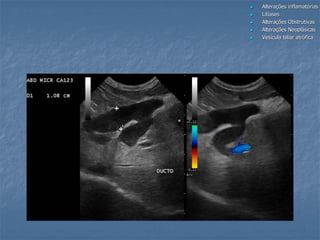

estômagoduodeno

DBC

duo

“plugs” no ducto biliar comum em gatos

Sem presença de sombreamento acústico

Remoção cirúrgica: concreções sólidas

Análise bioquímica: bilirrubina e colesterol